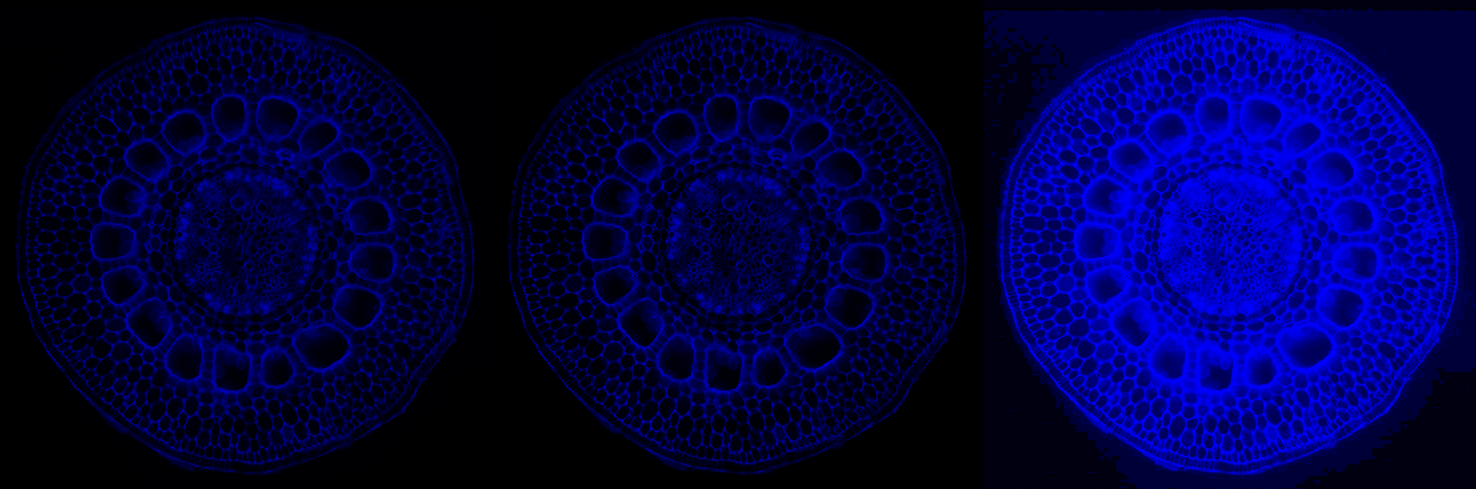

As mentioned above, it is hard (any potentially undesirable) to directly build a GDP from biomedical images. We hence learned the prior from natural-scene images, but validate it here on biomedical images. We first show stability of the present GDP for biomedical images. For this, we collected a small dataset of biomedical images, including X-ray, MRI, electron microscopy, and fluorescence microscopy images. Some examples are shown in Figs. 10 and 24.

9.1 Image naturalization

Remapping the gradient field of any image to match the GDP of natural-scene images, and then reconstructing the output image is called image naturalization, because the output image will have a gradient distribution that matches the one of natural-scene images. The naturalized output image hence looks more “natural”. The workflow is shown in Fig. 23. Since the GDP correlates with image quality, this makes the image look more appealing. We hence propose to use image naturalization as an alternative to histogram equalization when displaying images to a human observer. Image naturalization enhances contrast by solving Eq. 2 with hard GDP constraint. Some examples of microscopy images (left tile of each panel) and their naturalized versions (middle tiles) are shown in Fig. 24 along with the naturalness factor of the original image. The histogram-equalized images are shown in right tiles for comparison. The first row shows four fluorescence-microscopy images. The second row shows three electron-microscopy images and one fluorescence image. All images were collected from publicly accessible web pages; credits are in parentheses. Here we use the simple linear function, amounting to a straightforward rescaling of the image, albeit with a good, “natural” scale factor as determined by the GDP. In all cases. the naturalized image looks more appealing than the histogram-equalized image, and suffers from less background artifacts.